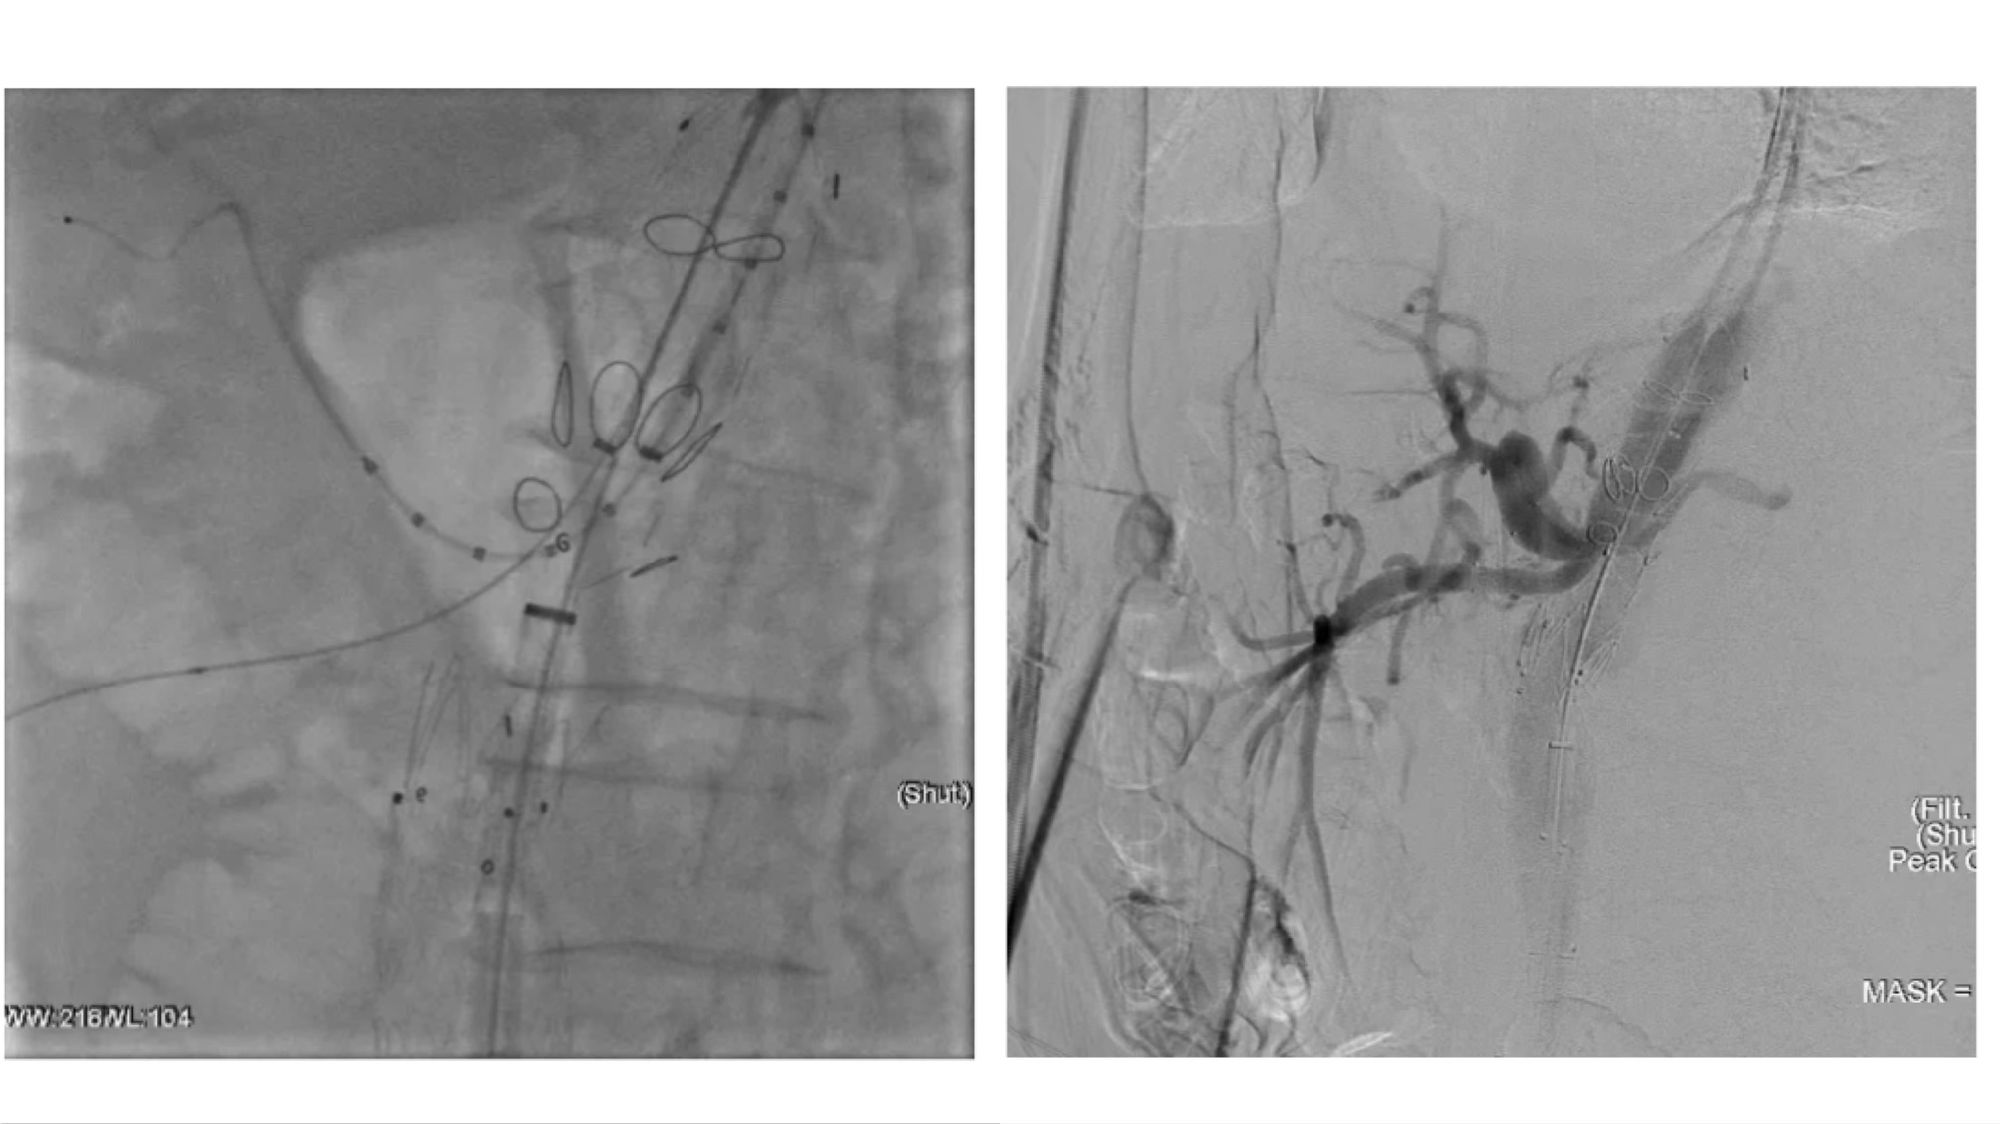

腔内重建腹腔干和肠系膜上动脉

腔内重建右肾和左肾动脉

(右肾开口处重度狭窄,左肾烟囱支架术后增加了手术难度)